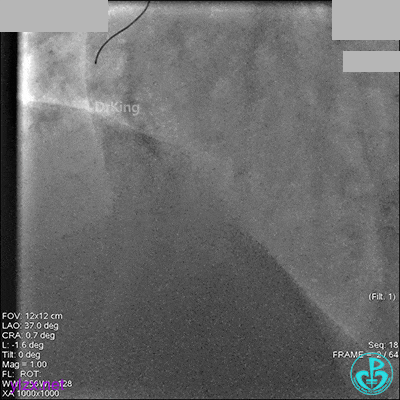

冠脉造影

入院次日冠脉造影显示粗大左主干末端中度狭窄,前降支开口严重狭窄,回旋支与前降支角度大,弥漫性长病变,严重狭窄,粗大右冠脉近中段弥漫性中重度狭窄。由于病变复杂,造影结束后先下台,择期再行介入治疗。